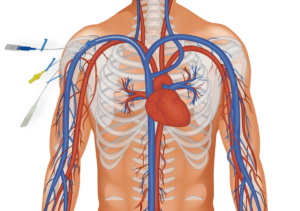

Les systèmes de gestion des fluides SpireWire® Fil de guidage PTCA

chirurgie générale et digestive Abords vasculaire

Abords vasculaire Chirurgie Orthopédique